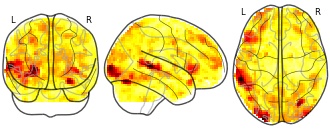

BrainPedia: devauchelle2009sentence_task001_sub025

EmailClick to copy linkLink copied Cite(2018). BrainPedia: devauchelle2009sentence_task001_sub025 [Dataset]. http://identifiers.org/neurovault.image:33753niftiAvailable download formatsUnique identifierhttps://identifiers.org/neurovault.image:33753Dataset updatedMay 7, 2018License

Cite(2018). BrainPedia: devauchelle2009sentence_task001_sub025 [Dataset]. http://identifiers.org/neurovault.image:33753niftiAvailable download formatsUnique identifierhttps://identifiers.org/neurovault.image:33753Dataset updatedMay 7, 2018LicenseCC0 1.0 Universal Public Domain Dedicationhttps://creativecommons.org/publicdomain/zero/1.0/

License information was derived automaticallyDescriptionCollection description

BrainPedia is a collection of SPMs obtained from about 30 protocoles from OpenfMRI, the Human Connectome Project and Neurospin research center that map a wide set of cognitive functions.

Subject species

homo sapiens

Modality

fMRI-BOLD

Analysis level

single-subject

Cognitive paradigm (task)

Sentence/nonword language localizer

Map type

Z